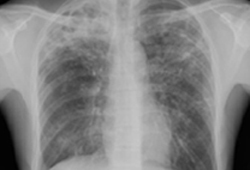

Radiografía de tórax portátil con opacidades bibasales, peor a la derecha que a la izquierda, en un paciente con neumonía adquirida en el hospital

De la colección personal del Dr. F. W. Arnold, División de Enfermedades Infecciosas, Departamento de Medicina, University of Louisville School of Medicine